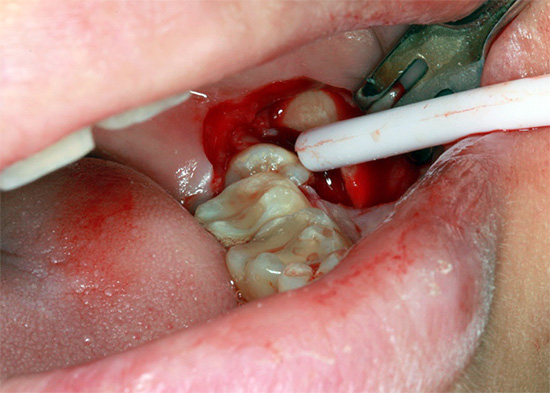

La foto sotto mostra le fasi iniziali della procedura per la rimozione del dente del giudizio retinirovannogo (cioè nascosto sotto la gomma):